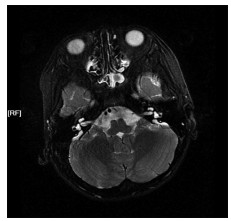

神经超声联合神经磁共振成像在吉兰-巴雷综合征诊断中的意义及机制研究

时鹏, 武心语, 怀玉水, 宋宏伟, 年娣

2025, 23(8): 1292-1297. doi: 10.16766/j.cnki.issn.1674-4152.004118

摘要:

目的  探讨神经超声联合神经磁共振成像在吉兰-巴雷综合征(GBS)患者诊断中的作用及机制。  方法  选取蚌埠医科大学第一附属医院2021年10月—2025年2月被诊断为GBS的患者43例,另选取24例健康体检者作为对照组。依据临床症状、体征及神经电生理检查将患者分为急性炎性脱髓鞘性多发神经根神经病(AIDP)和急性运动轴突性神经病(AMAN)两个亚型组,采用神经超声测量颈神经根、肢体周围神经横断面积(CSA);神经磁共振成像测量颈神经根、腰骶神经根CSA;吉兰-巴雷综合征残疾评分量表(GDSS)评估GBS患者神经功能缺失程度,分析CSA与神经缺损程度之间的相关性;收集外周静脉血,ELISA试剂盒测定外周血中细胞焦亡炎性因子水平。  结果  与对照组相比,AIDP组和AMAN组神经根、肢体周围神经增粗,CSA升高,其中神经超声示3组C5、C6比较差异均有统计学意义(H=20.216,P < 0.001;H=12.452,P=0.002);磁共振成像结果显示,与AMAN组和健康对照组相比, AIDP组患者C4~C8、L3~S1的CSA显著升高,差异均有统计学意义(P < 0.01);周围神经CSA与神经功能缺损程度呈正相关关系(P < 0.05);GBS患者外周血焦亡炎性因子水平较对照组升高,差异有统计学意义(P < 0.05)。  结论  GBS患者神经根和周围神经CSA值升高和神经功能缺损可能与焦亡途径激活导致的炎症级联反应有关,联合神经影像学和炎性因子检测有助于GBS的早期诊断,为GBS诊疗提供新思路。